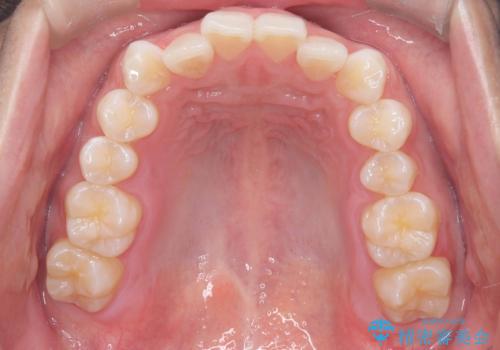

歯のデコボコを治したい|インビザラインで綺麗な歯並びに!|矯正期間は6ヵ月!

- 歯のデコボコが気になるを主訴に来院された患者様です。

インビザラインで歯は抜かずに非抜歯でデコボコを改善しました。

インビザラインで叢生の改善を行いました。

歯は抜かずに、拡大と少しのIPRで並べました。

矯正期間は半年です。

綺麗な歯並びを手に入れ大変ご満足していただきました。